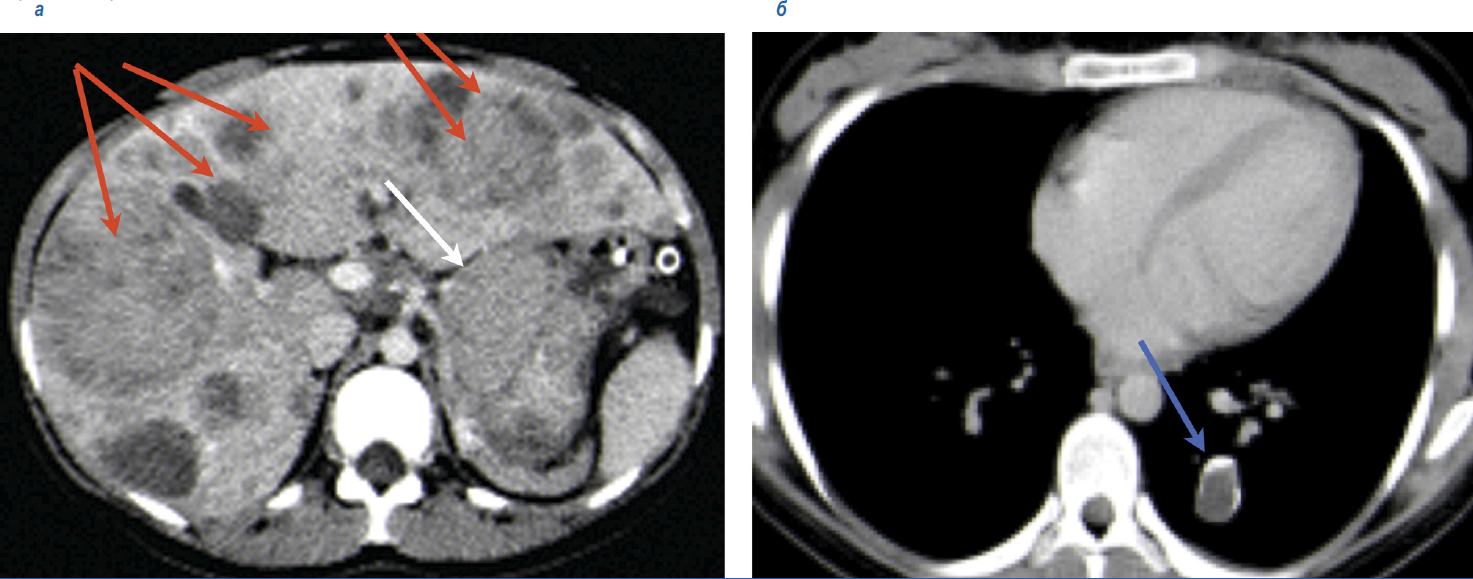

У пациентки К. 21 года при обследовании по поводу болей в правом подреберье в январе 2019 г. выявлены опухоль желудка с метастазами в печени и по брюшине, хондрома в левом легком (рис. 2). Выполнена биопсия метастаза в печени, при гистологическом исследовании – ГИСО эпителиоидноклеточного строения с положительной экспрессией CD-117. При молекулярно-генетическом исследовании мутаций генов C-KIT, PDGFRA не выявлено. При иммуногистохимическом (ИГХ) исследовании выявлен дефицит SDHB. Таким образом, у пациентки установлен диагноз неполной триады Карнея.

Рис. 2. Данные КТ до начала лечения: а – опухоль желудка (белая стрелка), а – метастазы в печени (красные стрелки); б – хондрома в левом легком (синяя стрелка).

Fig. 2. Computed tomography (CT) data before the treatment: a – the tumor of the stomach (white arrow), a – liver metastases (red arrows); b – chondroma of the left lung (blue arrow).

С января 2019 г. пациентка принимала иматиниб в дозе 400 мг/сут, который был назначен до получения результатов молекулярно-генетического и ИГХ-исследований. При повторном визите через 4 нед пациентка отметила улучшение общего состояния, в связи с чем, несмотря на полученные результаты молекулярно-генетического и ИГХ-исследований, было принято решение о продолжении терапии иматинибом. Через 2 мес терапии, в апреле 2019 г., по данным компьютерной томографии (КТ), отмечена положительная динамика – уменьшение размеров и плотности метастазов в печени и опухоли желудка (рис. 3).

Рис. 3. КТ в динамике на фоне приема иматиниба: а, в – до начала лечения, а – метастазы в печени, в – опухоль в желудке (февраль 2019 г.), б – через 2 мес терапии (апрель 2019 г.) – кистозная трансформация метастазов в печени, г – через 2 мес терапии, кистозная трансформация опухоли в желудке.

Fig. 3. Dynamic CT scanning against the background of applying imatinib: a, c – before the treatment, a – liver metastases, c – the tumor of the stomach (February 2019), b – after 2 months of therapy (April 2019) – cystic transformation of the liver metastases, d – after 2 months of therapy, cystic transformation of the tumor of the stomach.

Эффект длился с февраля по сентябрь 2019 г. При контрольном обследовании в сентябре 2019 г. выявлено прогрессирование заболевания, проявившееся ростом метастазов по брюшине в парагастральной области, при дальнейшем уменьшении метастазов в печени, уменьшении опухоли в желудке.